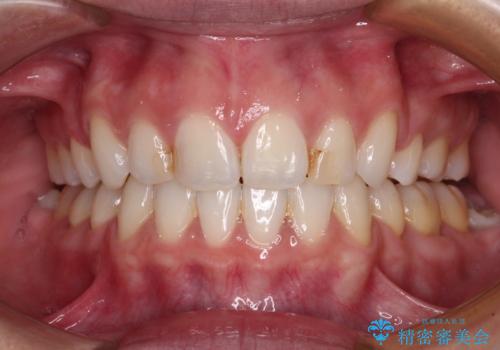

内側に転位した歯とボロボロのむし歯 インビザラインによる矯正治療とむし歯治療

矯正治療後には抜歯が必要な歯に隣接してむし歯となっていた歯をオールセラミッククラウンにて補綴治療を行うこととしました。

矯正治療開始時に、インビザライン矯正の加速装置を購入されましたが、インビザライン自体をあまりしっかりと使用できず、4年間の治療期間となりました。